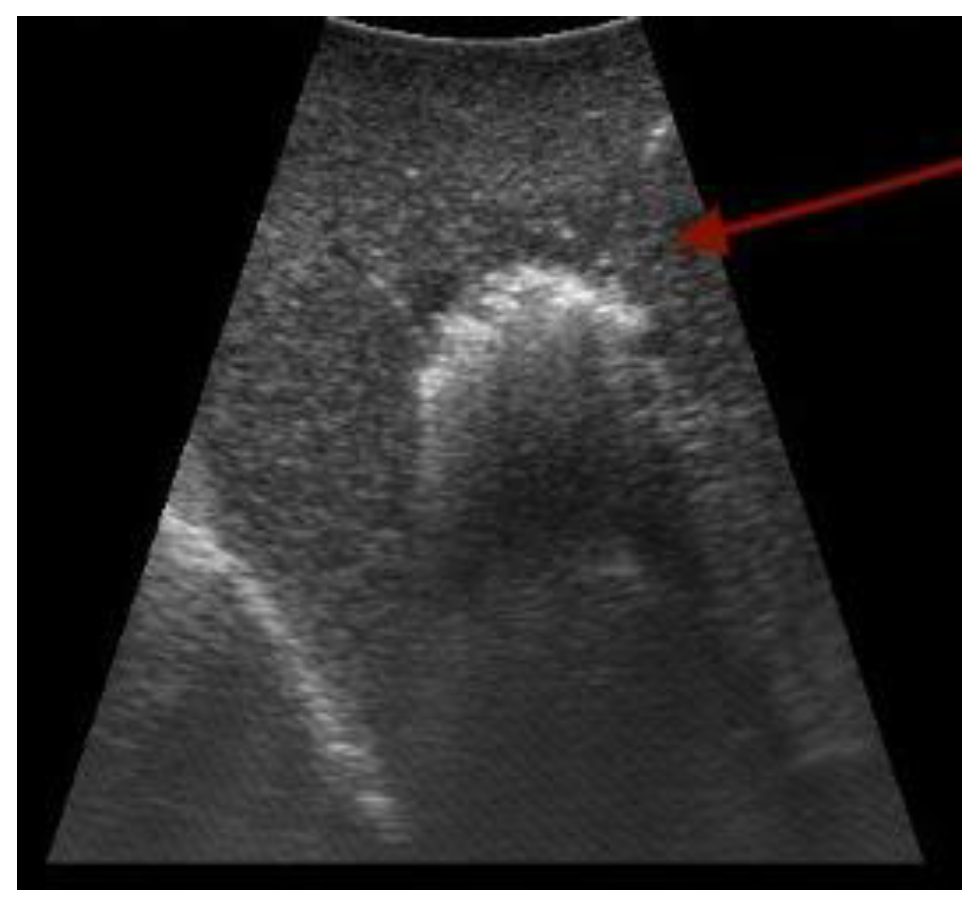

Figure 3.

Ultrasound-guided radiofrequency ablation in the liver (arrow points toward the needle). Original figure.